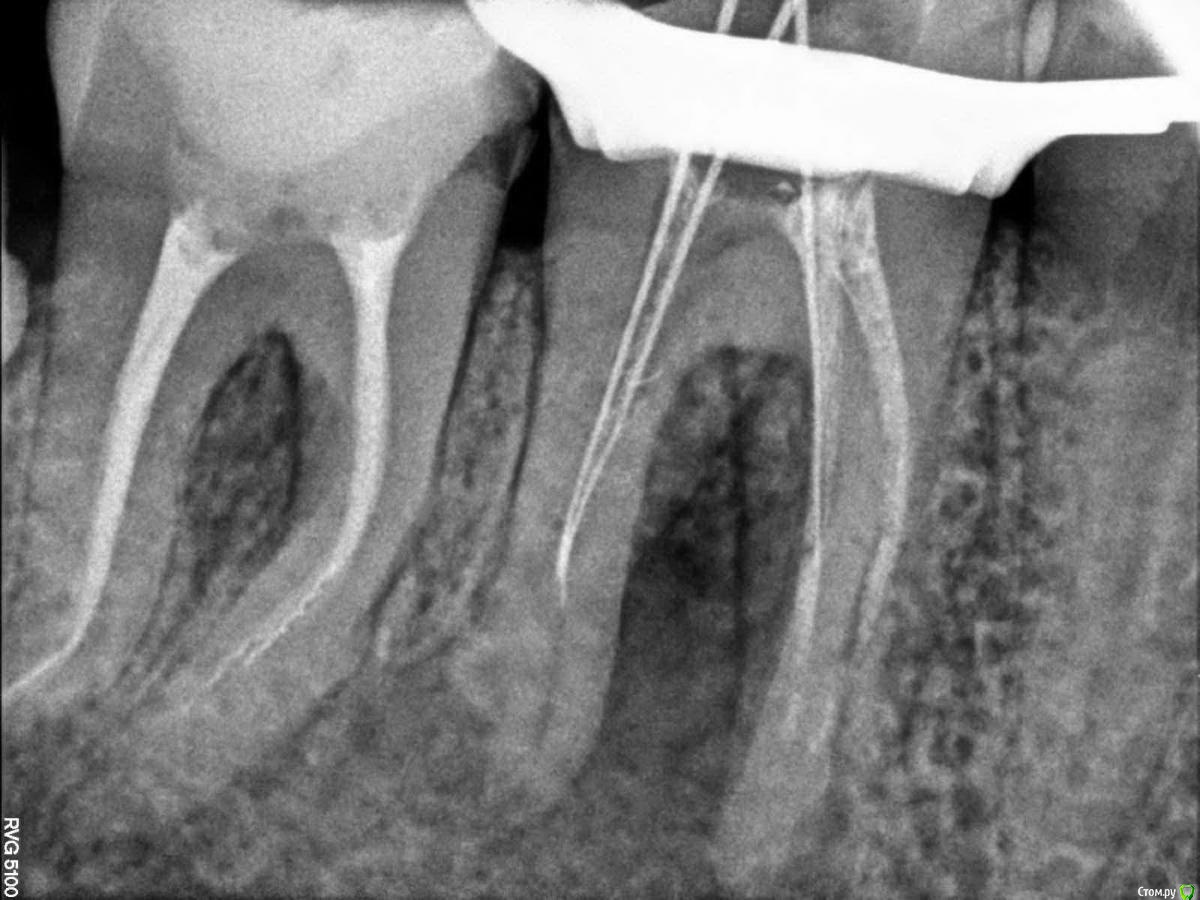

Bibika2020 Опубликовано 31 мая, 2020 Поделиться Опубликовано 31 мая, 2020 Всем добрый день. Предыстория:В 2018 году на зубе 46 откололся кусочек сзади и зуб начал сильно болеть. Зуб до этого был уже депульпирован лет 5-10 назад (уже не помню) и стоял со световой пломбой. В 2018 г. провели восстановление коронковой части зуба пломбой, в каналы не лазили.В 2019 году в районе этого зуба появился свищ, но зуб никак не беспокоил. Текущая ситуация:Весной 2020 года зуб начал реагировать на холодное и горячее и надкусывание средней степенью боли.Первое посещение врачаОбратился к врачу в марте (снимок 1 и 2). Доктор сказал, что можно попробовать перелечить каналы и сохранить зуб. Из трёх каналов один был не запломбирован, в двух других была гуттаперча. Доктор провела механическую и медикаментозную обработку двух каналов: незапломбированного и одного с гуттаперчей и заложила кальцийсодержащую пасту, поставила временную пломбу, выписала антибиотик 5 дней.Облегчение почувствовалось сразу. Через неделю свищ прошёл. Ещё через неделю опять появился. Второе посещение врачаКак раз подходило время очередного приёма, но доктор уже был другой в том же месте.Снимки 3 и 4. Доктор провела механическую и медикаментозную обработку двух каналов и заложила кальцийсодержащую пасту. Сказала, что временная пломба была сильно не герметична поэтому микробы попадали в зуб. Положила фум ленту и сделала световую пломбу 10 апреля. Свищ опять на какое-то время пропал и снова появился через пару недель. Третье посещение врачаНа следующем приёме доктор сделал снимок с гуттаперчей вставленной внутрь свища, на снимке гуттаперча дошла до низа левого канала, как раз того, который изначально не было запломбирован N лет назад (снимка, к сожалению, нет). Дальше подключился хирург и сказал, что такой зуб нужно удалять, т.к. гранулирующий периодонтит (если я правильно запомнил). Сейчас прошло почти 2 месяца есть неприятные ощущения от зуба и свищ то появляется, то пропадает. ВопросЗуб жалко удалять, на мой взгляд, он нормальный.Хотелось бы услышать мнение врачей, есть шанс сохранить зуб и что делать? Ссылка на комментарий

Bibika2020 Опубликовано 1 июня, 2020 Автор Поделиться Опубликовано 1 июня, 2020 (изменено) Вот ещё на снимке смущает (обвёл красным):1. на правых корнях 7го зуба волнистые линии это не остатки инструмента?2. непонятная загагулина на проблемном канале 6го зуба. что это может быть ? А что означает раскрытие полости зуба? Это его рассверливание, чтобы легче было к каналу доступ осуществить? Изменено 1 июня, 2020 пользователем Bibika2020 Ссылка на комментарий

dok1 Опубликовано 1 июня, 2020 Поделиться Опубликовано 1 июня, 2020 Щестёрка с булавоообразным утолщением корня. Пошла резорбция апекса. Плюс резорбция в просвете каналов. Я в шестой неверю . По этому бы рекомендовал удалить. Седьмой, если удастся извлечь инструмент, можно вылечить Ссылка на комментарий

Kolchanov Опубликовано 1 июня, 2020 Поделиться Опубликовано 1 июня, 2020 В Москве людей профессионально занимающихся эндодонтией куча. Процент успеха достаточно высок, чтобы пробовать сохранить. Но более точный ответ можно дать только на очной консультации, иногда после выполнения диагностического лечения (удаления временных вложений, попытки распломбировка каналов и т.д.).Дерзайте. Я лечил много стоматологов. Ни один себе зубы легко удалить не даст 2 Ссылка на комментарий